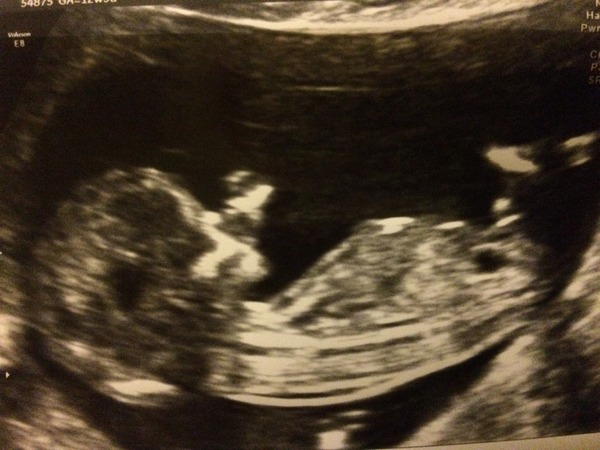

Back from my scan!

July 2016 (5)

Baby was lying in a good position and very calm, but we could hear a good strong heartbeat. It appears to be thumbing its nose at us!

Nuchal fold appeared to be within normal range. The hospital took two samples of blood, and will do a risk assessment with one, and only if it comes back high will do a DNA test with the other sample.

Thistledew - lovely pic!

Thistle fab scan!

Thistle lovely scan picture. Smile

Loving all the advice from moms already. Lovely scan pic thistle

Congrats on the scans, Thistle and Pinsey!